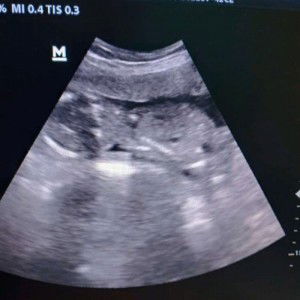

tensi rendah

Gara2kemaren banyak fikiran Tensi 80/60